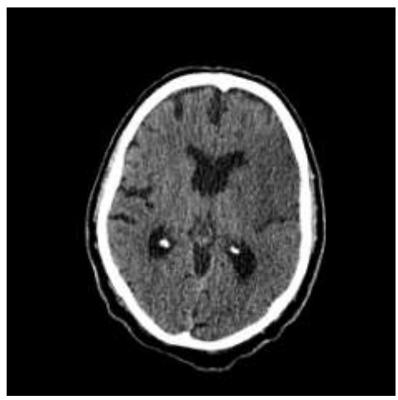

Tomografia de crânio